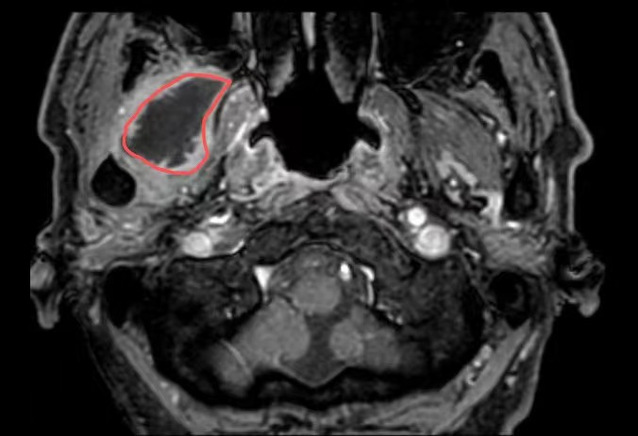

在探花直播 超声介入科,徐斌主任就接诊了这样一位患者。一个月前,患者熊先生脸颊部隐隐作痛,到医院一查是牙齿发炎了,抗炎后熊先生拔除了发炎的牙齿。但是,回家后没几天,面颊部就又开始疼痛、发热。经过反复就医、检查、消炎止痛后做增强磁共振提示:右翼外肌及颞肌异常信号,考虑脓肿可能,相关科室的医生和熊先生说这个手术可能比较复杂,需要行开放性手术。

△磁共振提示病灶(红圈处)